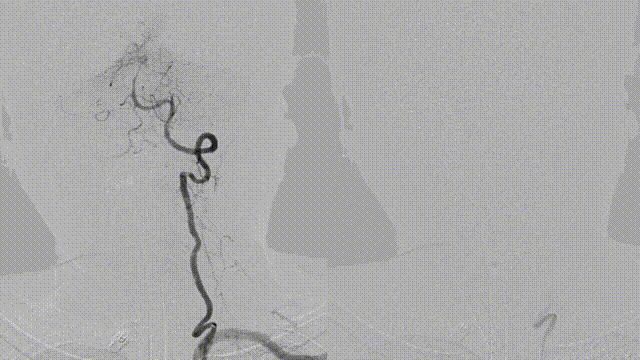

Left vertebral artery V1 segment was tortuous. A balloon-assisted DAC system was used to navigate through the tortuous segment. A 0.014-inch microwire failed to cross the occlusion due to torque control difficulty.

Switched to a 0.010-inch microwire, which successfully crossed the lesion and was advanced into the left superior cerebellar artery. Microcatheter angiography confirmed true lumen access. A Zenith Stent Retriever (4 mm × 20 mm) was deployed at the occlusion site.

After deployment of Zenith Stent Retriever, distal vessel branches reappeared. Post-thrombectomy angiography showed restored antegrade flow, but with residual severe stenosis.